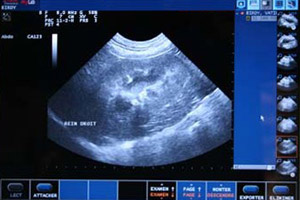

Echographie abdominale : L’échographie abdominale permet de visualiser certains organes non visibles en radiographie et de façon beaucoup plus précise. C’est devenu l’examen de choix pour explorer les maladies digestives, rénales, de l’appareil génital…

Durant l’échographie, il est possible de réaliser des prélèvements, par exemple prélever de l’urine de manière stérile pour rechercher des bactéries ou encore faire des prélèvements d’organes afin de les analyser. Dans certains cas cela permet de faire des biopsies avec une anesthésie très courte et sans opérer voter animal.